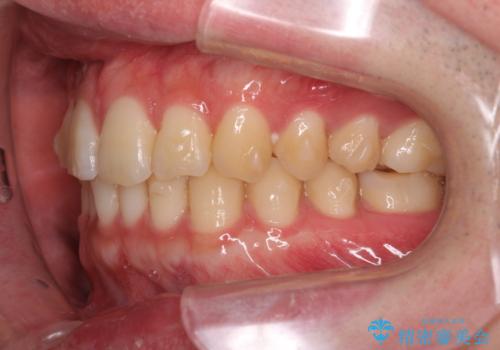

前歯のがたつきをなおしたい マウスピース矯正

- 気になる前歯のがたつきをきれいにしたい。と矯正治療を希望され来院されました。

大きな歯列の乱れはないため、倒れ込んでいる奥歯の傾きの改善、前歯のがたつきを改善する治療を計画します。

見た目が良くなっただけではなく、歯ブラシがしやすくなった!と治療後の歯並びに喜んでいただくことができました。